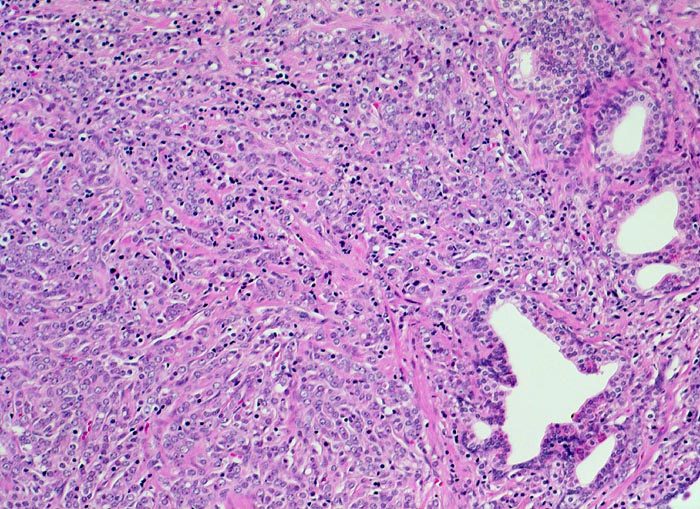

• Karzinomzellen mit stark erhöhter Kern-Zytoplasmarelation und hyperchromatischen Zellkernen mit grossen eosinophilen Nukleolen.

• Wenig differenzierte Karzinomanteile ohne erkennbare Drüsenbildung.